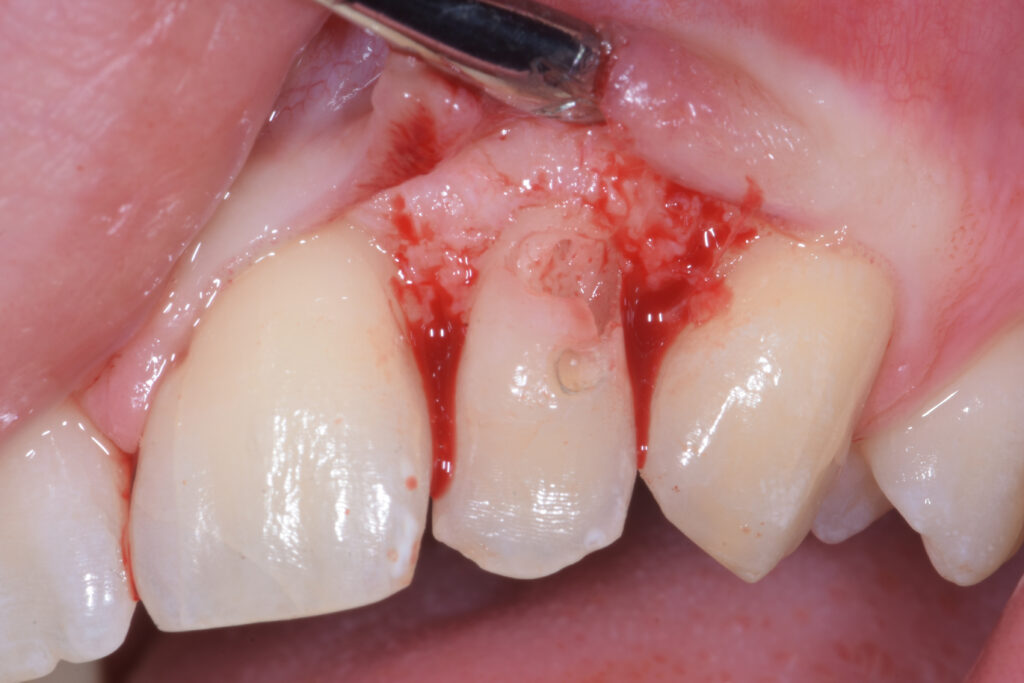

Previa anestesia plessica si esegue un lembo con incisione intrasulculare e scollamento sottoperiostale allo scopo di rendere visibile la reale estensione del danno (Figura 2).

Riassorbimento cervicale esterno